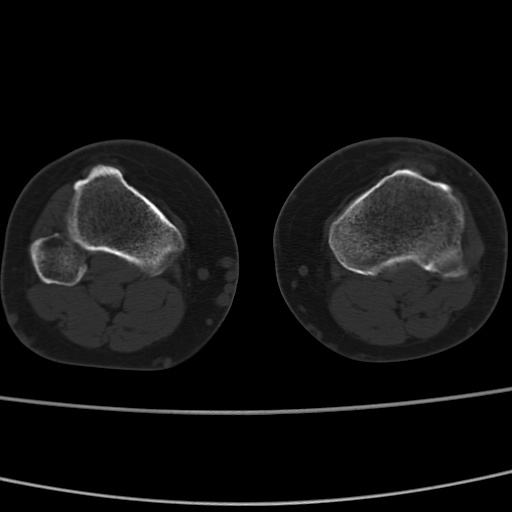

女性,50岁。【请提供患者临床症状体征】

右膝关节退行性改变,关节游离鼠。

右膝关节退行性改变,滑膜黏液囊钙/骨化并游离。